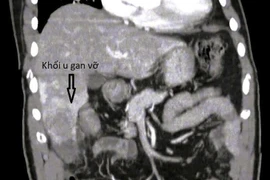

“Ngày 29 Tết, ngay trước thời điểm giao thừa, chúng tôi tiếp nhận một bệnh nhân bị phình tách động mạch chủ. Đây là tình trạng lớp áo trong của động mạch bị bóc tách, khiến dòng máu bơm đi không đầy đủ, làm chức năng tim mạch suy giảm rất nhanh. Đây là bệnh lý tối cấp cứu, nếu không xử trí kịp thời, bệnh nhân có thể tử vong trong thời gian rất ngắn”, ThS, ​BSNT Ngô Đức Hùng chia sẻ.

Trường hợp này buộc bệnh viện phải huy động nhiều chuyên khoa và nhiều kíp trực khác nhau. Bệnh nhân có chỉ định thay toàn bộ hệ thống quai động mạch chủ nhân tạo, từ tim tới ổ bụng. Đây là một đại phẫu rất lớn, kéo dài nhiều giờ trong ngày 29 Tết.

Sau mổ, tình trạng bệnh nhân tương đối ổn định và hiện vẫn đang được theo dõi tại khoa hồi sức. Đây là một nỗ lực rất lớn của toàn bộ ê-kíp trong điều kiện nhân lực trực Tết hạn chế.